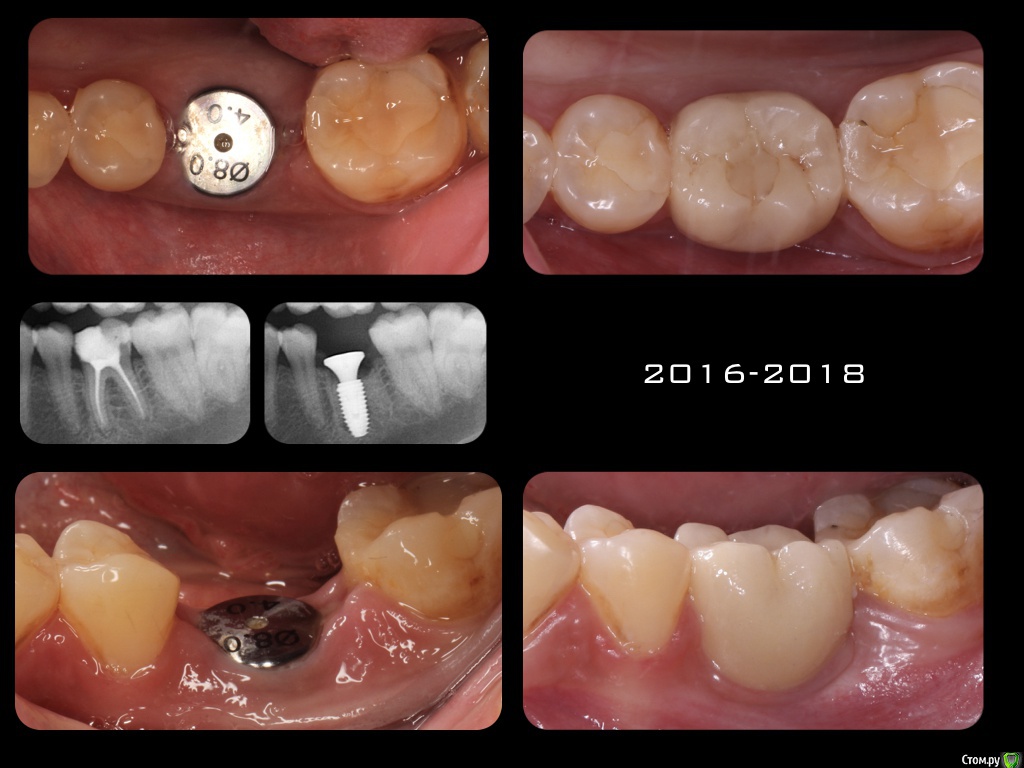

mann Опубликовано 24 мая, 2018 Автор Поделиться Опубликовано 24 мая, 2018 в продолжении ситуации, когда месяц назад установлен имплантат, над местом установки появился как-бы шарик. Я установил формирователь десны. Сейчас все хорошо. Сколько пациентке ходить с формирователем? До полной интеграции имплантата? Или выкрутить формик через какое-то время? Ссылка на комментарий

Nazim_NV86 Опубликовано 27 мая, 2018 Поделиться Опубликовано 27 мая, 2018 в продолжении ситуации, когда месяц назад установлен имплантат, над местом установки появился как-бы шарик. Я установил формирователь десны. Сейчас все хорошо. Сколько пациентке ходить с формирователем? До полной интеграции имплантата? Или выкрутить формик через какое-то время?Перед протезированием лучше сделать ревизию. С какого нибудь одного бока у импланта может оказаться грануляционная ткань. Очистив её вы поймете величину очага. Потом кость и фдм. Ссылка на комментарий